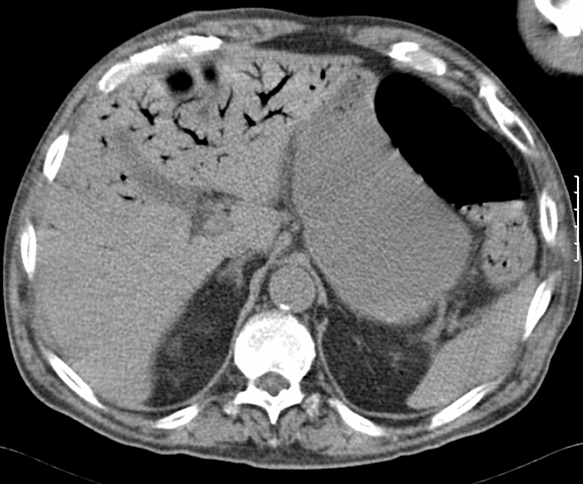

Doente de 60 anos, sexo masculino.

Operado a tumor neuroendócrino do íleon em 2003.

Ecografia abdominal. de Novembro 2008.

Answer to - Spleen Focal Lesions

Focal lesions of the spleen can be classified as benign or malignant. Benign lesions are more common, including cysts, infarcts, abscesses, haemangioma, hamartomas and calcifications. Malignant lesions are less frequent and include primary lymphoma, sarcomas and metastatic involvement.

Splenic metastases are very rare and most often appear asymptomatic. The literature reports an incidence in autopsy of 0, 6% and in splenectomy of 1, 1%. The most common primary tumour sites are breast and lung, followed by GI tract tumours (oesophagus, stomach and colon), along with few female reproductive organ malignancies (ovary), head and neck neoplasias (pharyngeal) and malignant melanoma. They may appear as a unique focal lesion or multiple lesions within the spleen. Splenic metastases are usually part of wide-spread disseminated malignancies however primary lesions can also occur.

On CT splenic metastases are round masses, very well circumscribed, spontaneously hypodense and fail to enhance after the IV contrast uptake. Carcinoid tumours in general tend to be hypervascularised and may demonstrate intense enhancement during arterial phase. However, spleen metastases from primary neuroendocrine can appear isodense or slightly hyperdense after contrast uptake, since the healthy spleen normally demonstrates heterogeneous enhancement during the parenchymal phase of opacification.

On ultrasound most splenic metastases may appear similar to those depicted in the liver. Most often they have round and well circumscribed shape and are usually hypoechoic. Despite splenic lesions with increase of echogenicity are uncommon in patients with lymphoma, they can often develop as metastatic involvement from neuroendocrine cancers. Commonly these metastases may increase the overall spleen size as well as causing complains of compression or further capsule rupture.

At MRI splenic metastases are typically hyperintense nodules or masses on T2-weighted images and hypo / isointense on T1-weighted sequences. The degree and characteristics of enhancement depend on the nature and type of the underlying primary neoplasm. These features are also applicable to carcinoid tumours.

The SPECT often depicts splenic enhanced spots attributable to metastatic disease.